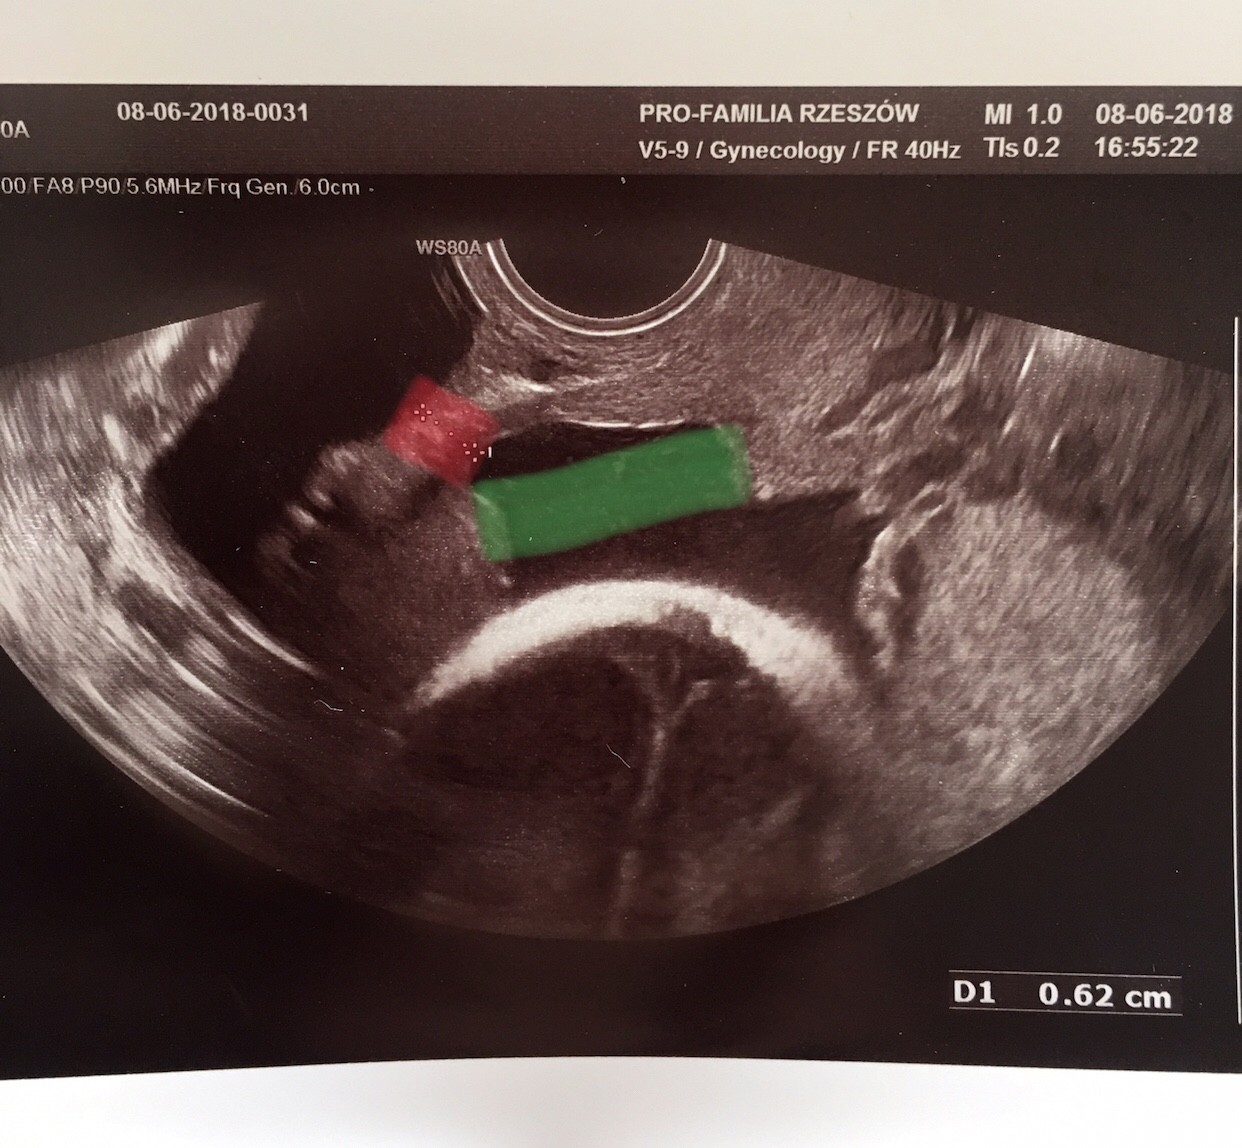

Zobacz załącznik 870168

Na czerwono to co trzyma na zielono to co puscilo i zrobila sie taka „dziura”

Aa to te 62mm to szerokosc dziury ??? Tobie sie to juz rozeszlo??.....czy te 62 mm to grubosc blizny??